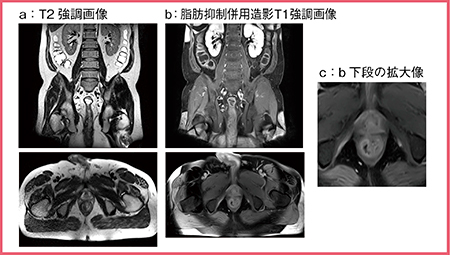

また,脂肪抑制に優れている点も大きな特長である。これは,“H-Sinc”という同社独自の技術によるものであり,CHESSパルスを複数回印加するなどしてRFパルスを最適化し,RF照射不均一の影響を低減することで,広範囲で均一な脂肪抑制効果が得られる。クローン病では肛門周囲膿瘍を合併することがあるため,肛門周囲の病変を検出できることが重要であるが,肛門はMRECの撮像範囲ぎりぎりに位置するため,どうしても脂肪抑制のムラが生じる(図2 b)。しかし,MREC画像を拡大すると,病変のある中央部分は脂肪抑制が良好であり,十分に評価可能である(図2 c)。

図2 優れた脂肪抑制効果を生かした肛門周囲膿瘍の評価